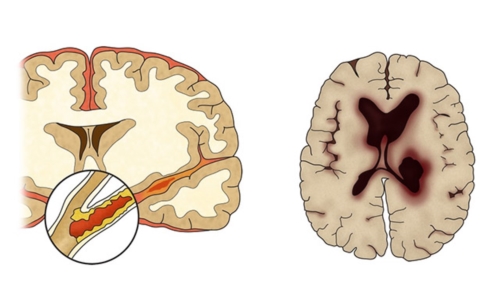

뇌혈관이 막히거나 터지는 질환을 통칭하는 것이 뇌졸중이고 그 중 뇌혈관이 막히는 것이 뇌경색 그리고 뇌혈관이 터지는것을 뇌출혈이라고 합니다. 뇌졸중은 영구적인 손상이 많고 증상에 따라 전신이나 신체 일부 기능이 마비되는 등의 심각한 후유증이 남는 무서운 질병인데요 오늘은 뇌경색 초기증상 및 뇌경색 치료방법에 대해 알려드리겠습니다.

건강보험심사평가원 자료에 따르면 뇌출혈로 병원을 찾은 환자보다 뇌경색으로 내원한 환자가 5배 이상 많았다고 하는데요 뇌경색은 뇌로 통하는 혈관이 막히면서 뇌 조직이 점차 괴사하게 되는 질환으로 날씨가 추워지는 겨울철에 특히 발생 가능성이 높은데요 혈관이 수축 하게 되면서 혈압 상승으로 이어지면서 뇌혈관 질환이 발생하게 되기 때문입니다.

뇌경색 원인은 동맥경화증으로 시작합니다. 병이 든 혈관 어떤 곳에든 핏덩어리가 생겨나면 심장에서 뇌로 흐르는 혈액의 흐름을 방해하게 됩니다. 만약 핏덩어리가 내경동맥이나 뇌혈관을 막게 되면 치명적인 뇌 손상을 입을 수 있습니다. 이렇듯 갑자기 혈관을 막는 경우도 있으나, 혈전에 의하여 점차 혈관 너비가 좁아지면서 허혈성 뇌졸중이 유발되는 경우도 있습니다.